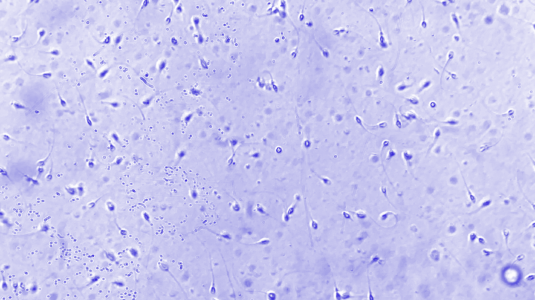

The first step in male fertility testing is the semen analysis. A semen analysis is a fairly simple, non-invasive test in which a semen sample, typically produced via masturbation, is examined under a high-powered microscope to determine the quantity and quality of sperm.

Sperm motility refers to how sperm move. Sperm are propelled forward by flagellations of their tail, plus a little help from the female reproductive system. The movement of sperm impacts whether or not they make it to the egg, and—once they do make it—whether they can penetrate the egg to fertilize it.

The ideal way for sperm to move is in straight lines or in large, sweeping circles. Motility is a measure of what percentage of sperm are moving, and progressive motility is a measure of what percentage of sperm are moving in this optimal way. According to the WHO, at least 40% motile sperm (with at least 32% moving progressively) is a normal result.

Sperm morphology (shape, size, and structure)

If a sperm is deformed—if it has multiple heads or tails, no head or tail, improperly formed sections, or it’s too big or too small—it may have difficulty moving toward the egg or fertilizing it. Morphology is the measure of what percentage of sperm have the proper shape, size, and structure, also known as “normal forms” (NF). According to the WHO, a normal morphology result is 4% NF or higher.